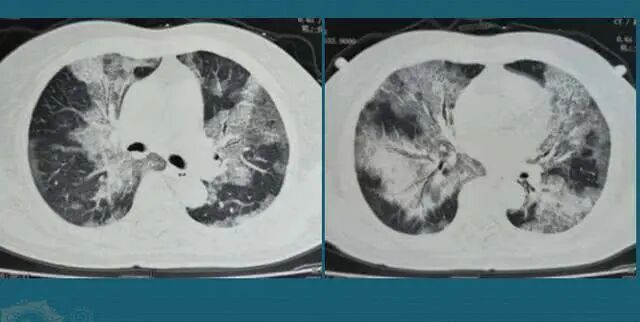

从死亡者病症看,大多是大白肺,问题是三年了,那个德尔塔究竟躲在哪里?为什么一说放开就马上出来了,还能混搭130多个品种?那么多专家为何这时又不发声了?这究竟是怎么回事?卫键委也没有说出个知乎所以然,究竟是奥密克戎还是2019年的新冠病毒?如果是奥密克戎为何和方舱里感染的人症状和疼痛感不同?如果是2019年的病毒一样,这个病毒是哪里来的?究竟是谁放的?